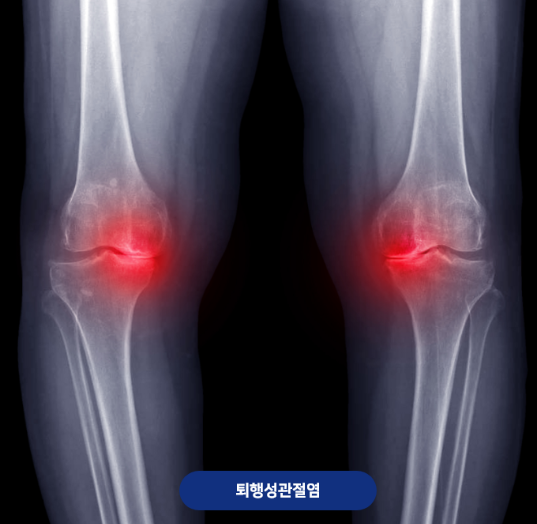

EBS명의에서는 퇴행성무릎관절염에 관한 내용이 방송되었는데요. 오늘은 관절염과 명의 박관규 교수에 대해 알아보겠습니다.

무릎 퇴행성 관절염이란?

무릎 퇴행성 관절염(Osteoarthritis of the knee)은 관절을 덮고 있는 연골이 나이가 들거나 외상, 과체중 등의 요인으로 점차 닳아 없어지면서 뼈와 인대에 손상을 일으키고, 그 결과 통증·염증·변형이 발생하는 질환입니다.